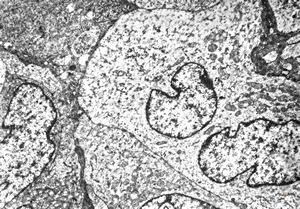

F,31y. | hypertrophic demyelinating neuropathy - n.suralis

M,13y. | n. suralis - hypertrophic demyelinating neuropathy